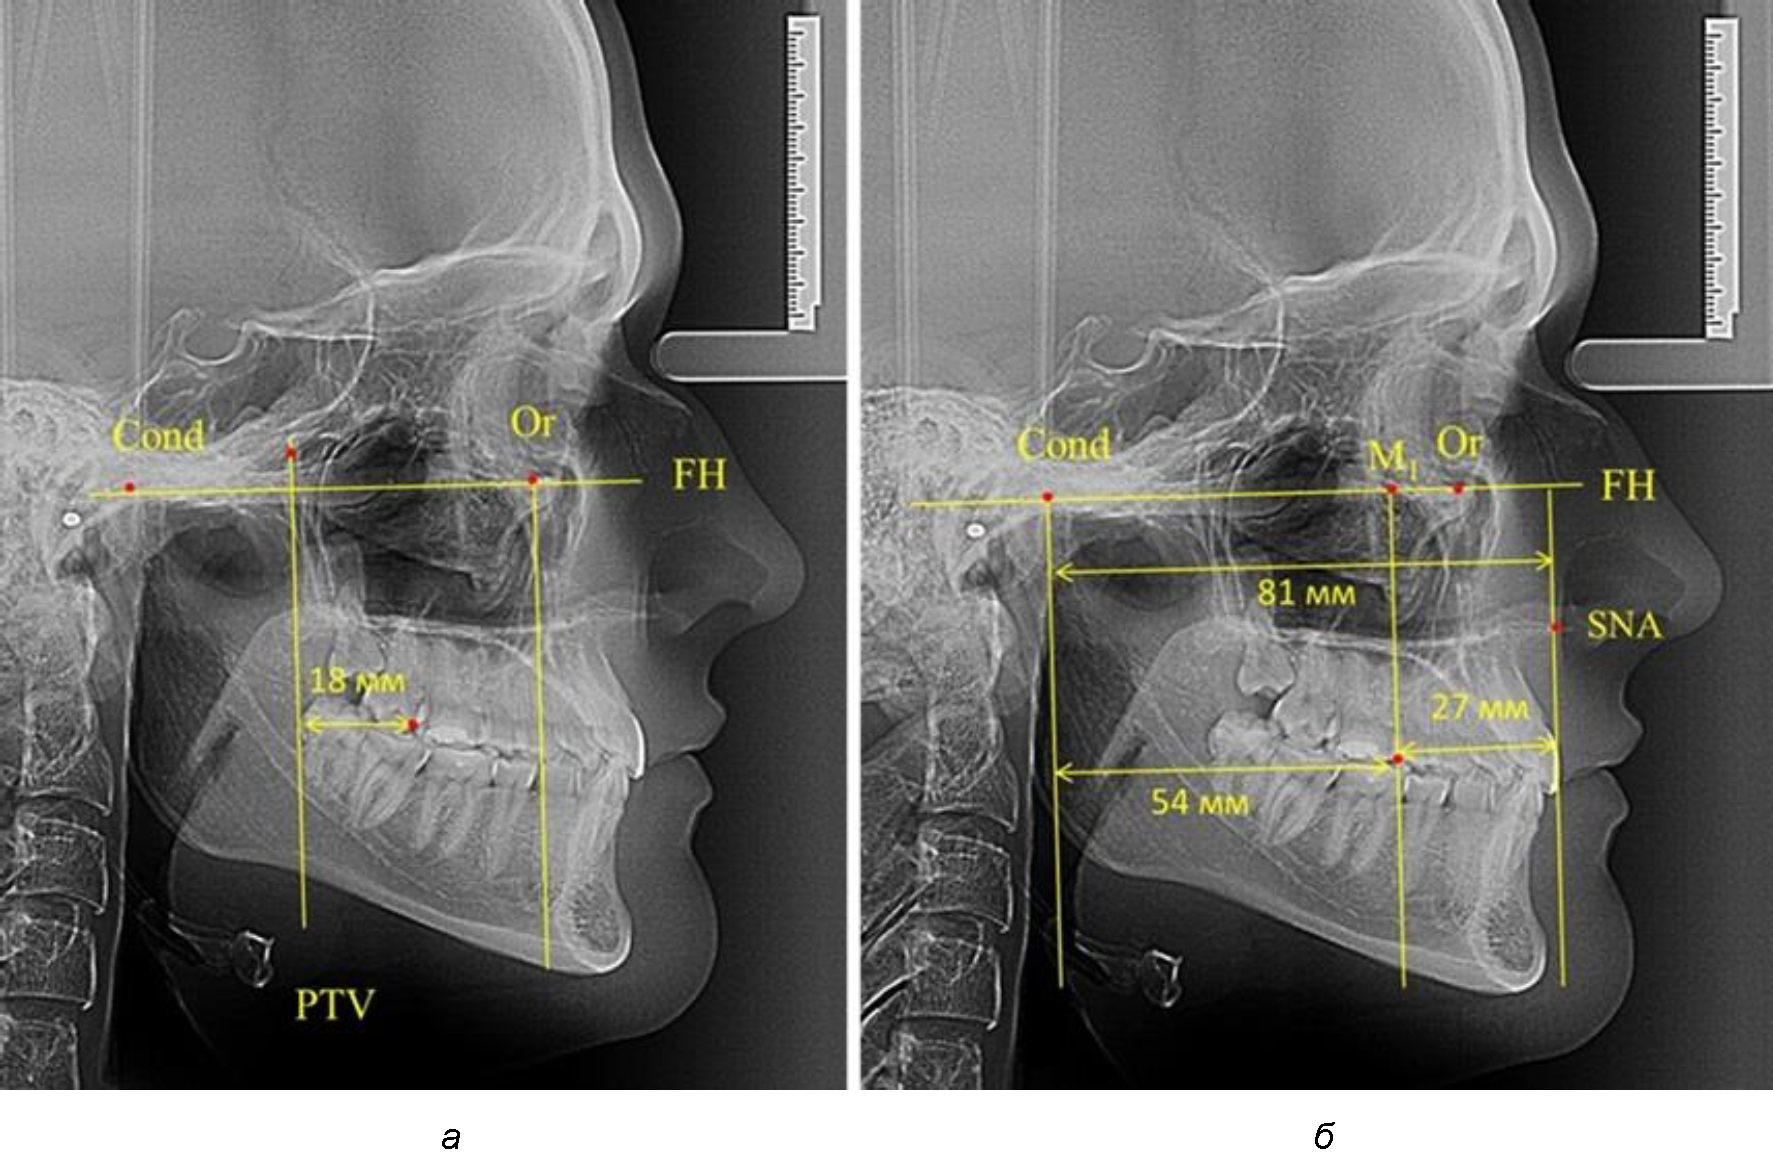

Рис. 2. Особенности положения первых моляров по R. E. McDonald (а) и по предложенному методу (б) при уменьшенном молярно-крыловидном расстоянии

Так, при расстоянии от крыловидной вертикальной плоскости PTV до дистальной поверхности верхнего первого постоянного моляра в 13 мм сагиттальный размер гнатического отдела был 82 мм. При этом отношение кондилярно-спинального расстояния к кондилярно-молярному размеру (54,5) было близким к коэффициенту 1,5, что представлено на рис. 2.

Таким образом, для прогнозирования оптимального положения первых постоянных моляров наиболее целесообразным методом явилось использование относительного показателя, что подтверждено при анализе рентгенограмм с минимальными и максимальными значениями по методу R. E. McDonald.

Среди анализируемых рентгенограмм минимальное значение расстояния по методу R. E. McDonald было 12 мм, а максимальное достигало 25 мм, что, по нашему мнению, обусловлено вариабельностью сагиттального размера гнатического отдела лица.

Анализ проведенного исследования рентгенограмм показал существенную вариабельность практически всех линейных показателей. У молодых людей с физиологическим прикусом постоянных зубов расстояние от крыловидной вертикальной плоскости PTV до дистальной поверхности верхнего первого постоянного моляра в целом по группе составляло (18,37 ± 3,62) мм. Обращает на себя внимание большая ошибка репрезентативности из-за разницы между максимальными и минимальными значениями.